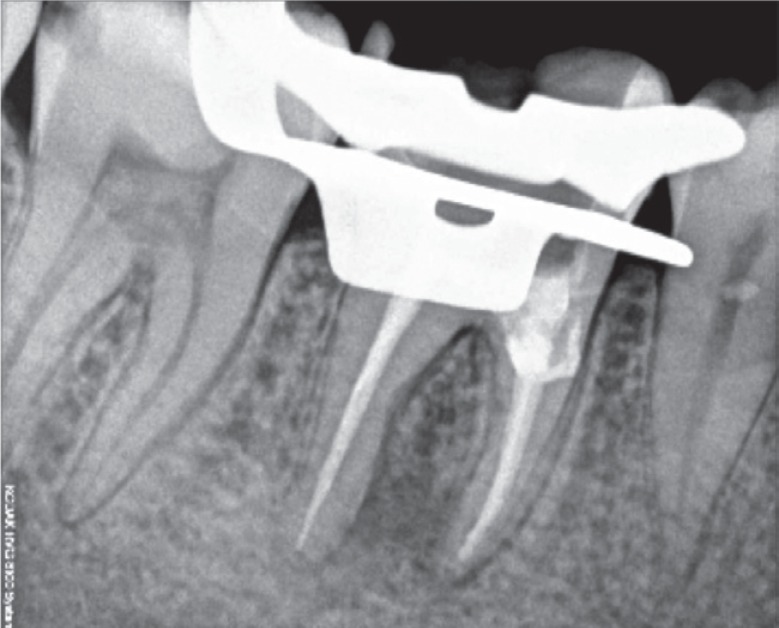

Figure 4Master cone length radiograph.